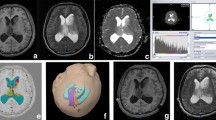

Diffusion spectrum imaging was performed in 122 meningiomas (30 males, 13–84 years), which were divided into 31 high-grade meningiomas (HGMs, grades 2 and 3) and 91 low-grade meningiomas (LGMs, grade 1). The histogram features of multiple diffusion metrics obtained from diffusion tensor imaging (DTI), diffusion kurtosis imaging (DKI), mean apparent propagator (MAP), and neurite orientation dispersion and density imaging (NODDI) in the solid tumours were analysed. All values between the two groups were compared with the Man-Whitney U test. Logistic regression analysis was applied to predict meningioma grade. The correlation between diffusion metrics and Ki-67 index was analysed.

The DKI_AK (axial kurtosis) maximum, DKI_AK range, MAP_RTPP (return-to-plane probability) maximum, MAP_RTPP range, NODDI_ICVF (intracellular volume fraction) range, and NODDI_ICVF maximum values were lower (p < 0.0001), whilst the DTI_MD (mean diffusivity) minimum values were higher in LGMs than those in HGMs (p < 0.001). Amongst the DTI, DKI, MAP, NODDI, and combined diffusion models, no significant differences were found in areas under the receiver operating characteristic curves (AUCs) for grading meningiomas (AUCs, 0.75, 0.75, 0.80, 0.79, and 0.86, respectively; all corrected p > 0.05, Bonferroni correction). Significant but weak positive correlations were found between the Ki-67 index and DKI, MAP, and NODDI metrics (r = 0.26–0.34, all p < 0.05).